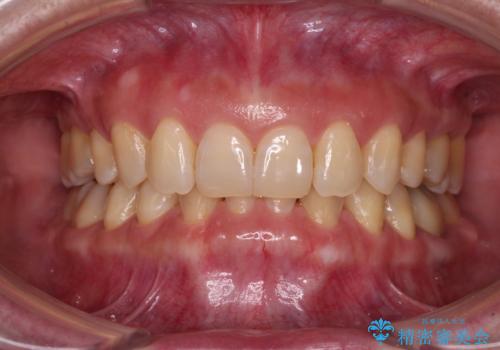

下顎2前歯の欠損 インビザラインによる抜歯矯正

マウスピースでの抜歯矯正特有の抜歯スペースに向かって奥歯が傾斜する動きが顕著に表れ、ディープバイトは改善されませんでした。

前歯のみが強く接触し、奥歯で咬めない期間も続いたため、ワイヤー装置などを補助的に使用し、何とか終了させることができました。